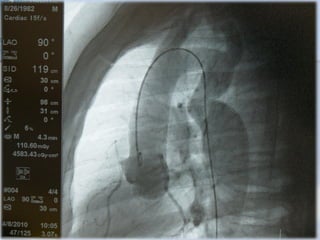

Ventriculografía

Ventriculografía Izquierda

Proyección OAD

Catéter Pig-Tail y Amplatz

INFORMACIÓN

- Contracción global y segmentaria

- Fracción Eyección (%)

- Competencia válvula Mitral

- Comunicación interventricular